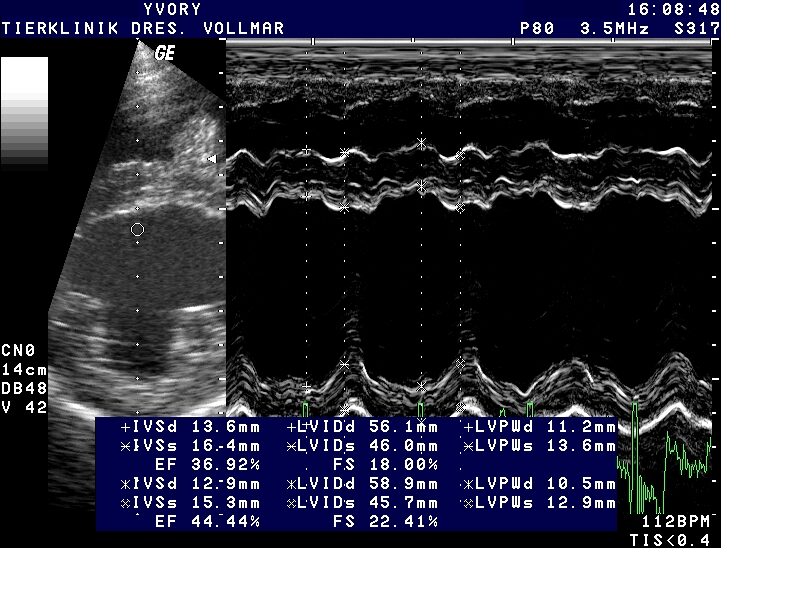

Bei der dilatativen Kardiomyopathie (DCM) ist die Herangehensweise anders als bei MI. Die DCM tritt bei vielen größeren Hunderassen als Erberkrankung auf und unterscheidet sich bei verschiedenen Hunderassen in vielerlei Hinsicht, so auch im klinischen Erscheinungsbild und im Verlauf. Als auskultatorisch hinweisende Befunde kommen bei einigen Rassen zwar früh im Krankheitsverlauf Arrhythmien in Form von Extrasystolen oder Vorhofflimmern vor, häufig ist die Auskultation aber unauffällig. Leise Herzgeräusche entstehen erst spät im Krankheitsverlauf mit Entwicklung einer sekundären AV-Klappeninsuffizienz durch Dilatation des Anulus fibrosus und Papillarmuskelatrophie Daher basiert die Früherkennung allein auf der echokardiografischen Untersuchung, je nach Rasse ergänzt durch EKG-Befunde bis hin zum 24-Stunden Holter-EKG.

Dilatativen Kardiomyopathie (DCM)

Besonders betroffene Rassen wie Dobermänner, Deutsche Doggen, Irische Wolfshunde, sollten ab dem jungen Erwachsenenalter regelmäßig kardiologisch untersucht werden - nicht nur aus zuchthygienischen Gründen, sondern auch, um dem Individuum möglichst lange eine gute Lebensqualität zu ermöglichen und die Lebenserwartung zu verbessern. Wie Erfahrungen aus der Humanmedizin und inzwischen mehrere veterinärmedizinische Studien zeigen, muss das vorrangige Ziel sein, die Erkrankung möglichst früh im präklinischen Stadium zu diagnostizieren und eine frühzeitige Therapie zu beginnen.